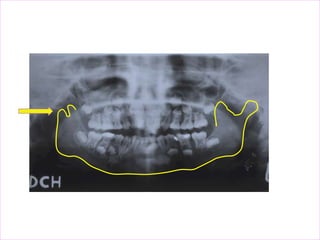

1) Palatoglossal air space

2) Nasopharyngeal air space

3) Glossopharyngeal air space